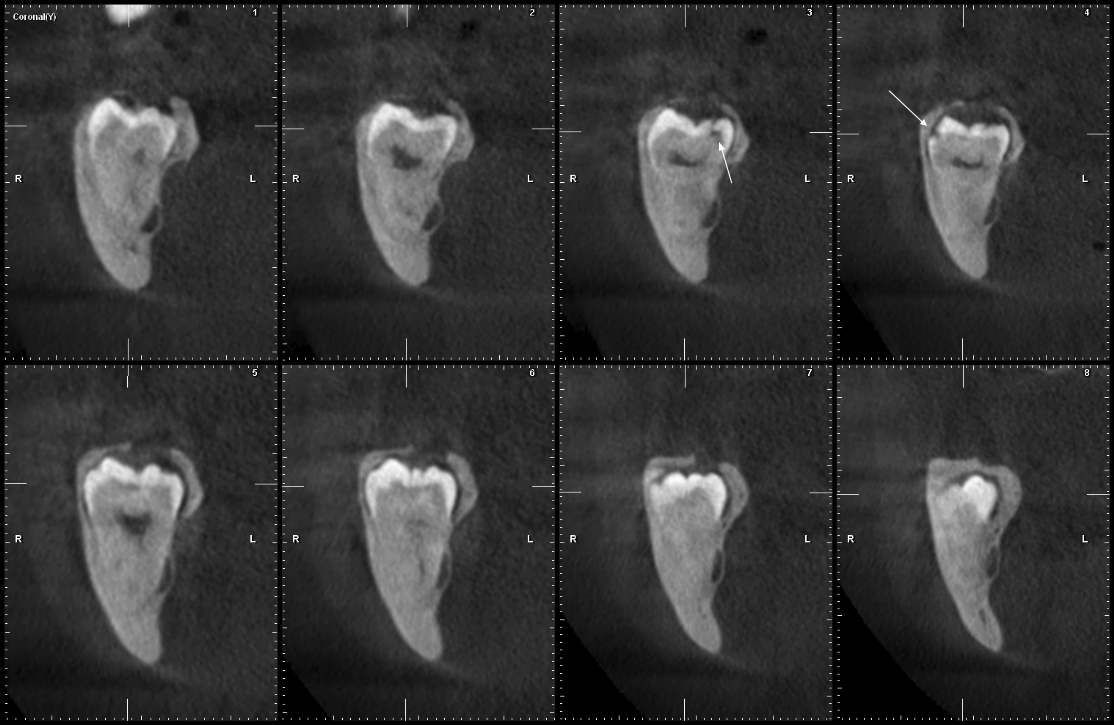

Se muestra la radiografía panorámica de una paciente femenina de 15 años de edad, en la que se observa la presencia de un defecto de RIPE de forma triangular bajo el esmalte de la cúspide distal de la pieza 38, de localización central y profundidad dentinal grado I (figura 6). En la THC adquirida, con un tamaño de vóxel de 0,2 mm, se observó un defecto dentinal de forma triangular y de grado I de profundidad, localizado en la cúspide distobucal, además de un defecto hipodenso del esmalte adyacente al defecto (figura 7).

Se tiene la radiografía panorámica de una paciente femenina de 45 años de edad, en la que se observa un defecto de RIPE en la pieza impactada 48, de localización mesial y profundidad dentinal de grado I, y, además, un segundo defecto ubicado en el centro de la corona y de forma alargada, que sería consistente con una fosa vestibular (figura 8). En la THC adquirida, con un tamaño de vóxel de 0,2 mm, se observó que el aparente defecto de RIPE mesial era, en realidad, la fosa mesiobucal y, además, se encontró un defecto de RIPE, grado I, en la cúspide distolingual asociada a un defecto hipodenso del esmalte adyacente al defecto (figuras 9, 10 y 11).

Los casos presentados constan de radiografías panorámicas y de THC, las cuales nos permitieron evaluar las superficies afectadas sin la superposición de estructuras anatómicas. Las radiografías panorámicas y bitewings fueron las técnicas radiográficas más utilizadas en el estudio de las características de la RIPE; la radiografía panorámica muestra en una sola toma todas las piezas erupcionadas y sin erupcionar, aunque las piezas anteriores, las premolares y molares maxilares, no se muestran de una manera adecuada; mientras que la THC puede demostrar la extensión real de los defectos (1). En todos los casos presentados, la THC ha demostrado la coexistencia del defecto dentinario y el defecto de esmalte; este signo tomográfico debería ser tomado en cuenta para estudios posteriores y en la planificación del tratamiento.

La presencia de defectos de RIPE junto a defectos de esmalte ha sido reportada por McNamara et al. (8), Kjær et al. (9) y Lenzi et al. (10). La formación de esmalte es inducida por la dentinogénesis e inicia a nivel de las cúspides, siguiendo una dirección cervical (11); la demostración tomográfica de los defectos de esmalte y dentina en las piezas afectadas por RIPE sugieren que los defectos podrían ser el resultado de la ausencia localizada de formación dentinaria, que determinaría la ausencia de formación de esmalte o el resultado de la migración de células de resorción a través de los defectos de esmalte (5, 6).

Al-Batayneh et al. (1) enfatizaron la importancia del diagnóstico tomográfico de los casos de RIPE. En los casos presentados, la discrepancia encontrada entre la radiografía panorámica y la THC podría ser determinante al momento de la planificación del tratamiento; se podría considerar la ampliación de estudio con THC en los casos confirmados de RIPE, para que se pueda determinar la extensión real del defecto y la decisión de intervención o espera.